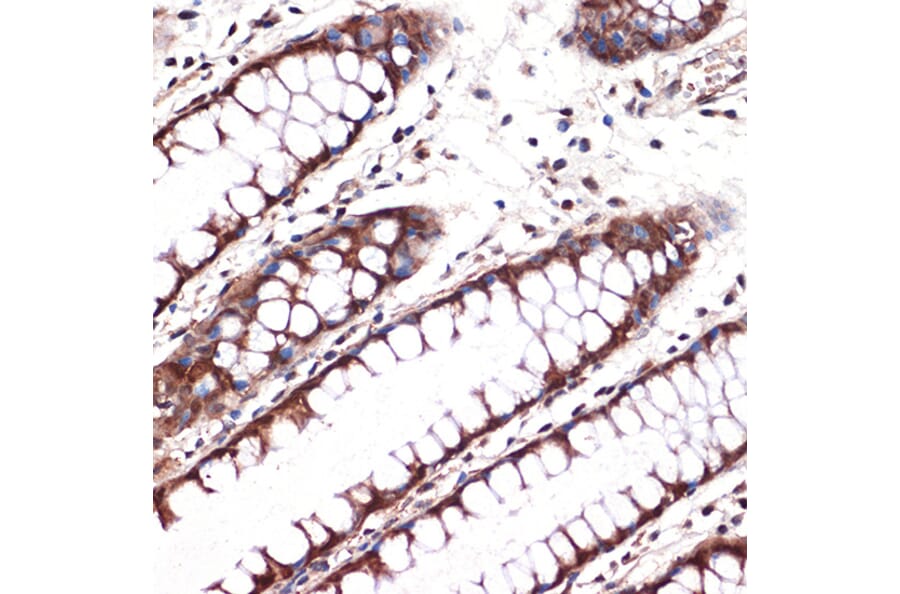

Immunohistochemistry analysis of paraffin-embedded human colon tissue using Anti-Carbonic anhydrase 2/CA2 Antibody [ARC1451] (A305662) at a dilution of 1:100 (40x lens). Perform microwave antigen retrieval with 10 mM Tris/EDTA buffer pH 9.0 before commencing with IHC staining protocol.